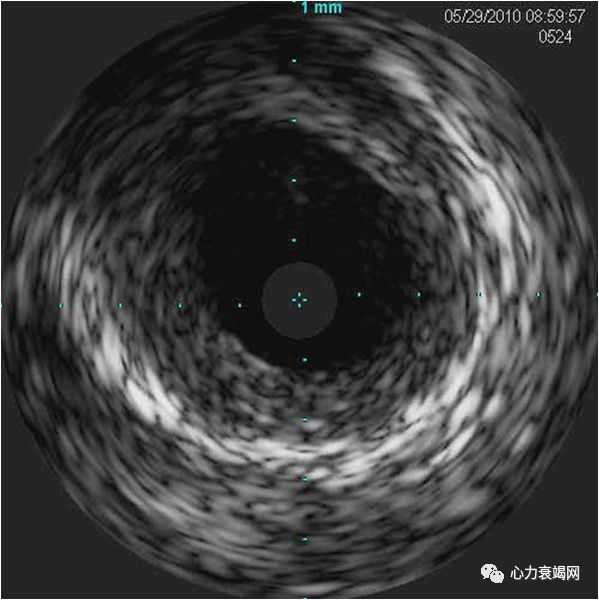

F/63

间断胸痛2月余,憋气伴双下肢水肿1月

血常规:

WBC11.81*10^9/L,EOS 4.14*109/L,EOS%35%,便寄生虫(-)*3

T-IgE 569.0KU/L↑

CTnI 1.12 → 2.67ng/ml;BNP378ng/L

支气管哮喘十余年。对花粉等多种物质过敏。

胸片:左肺中野团絮状高密度影,边界不清,双侧胸腔积液;

冠脉造影:右冠轻度动脉硬化,前降支、回旋支大致正常